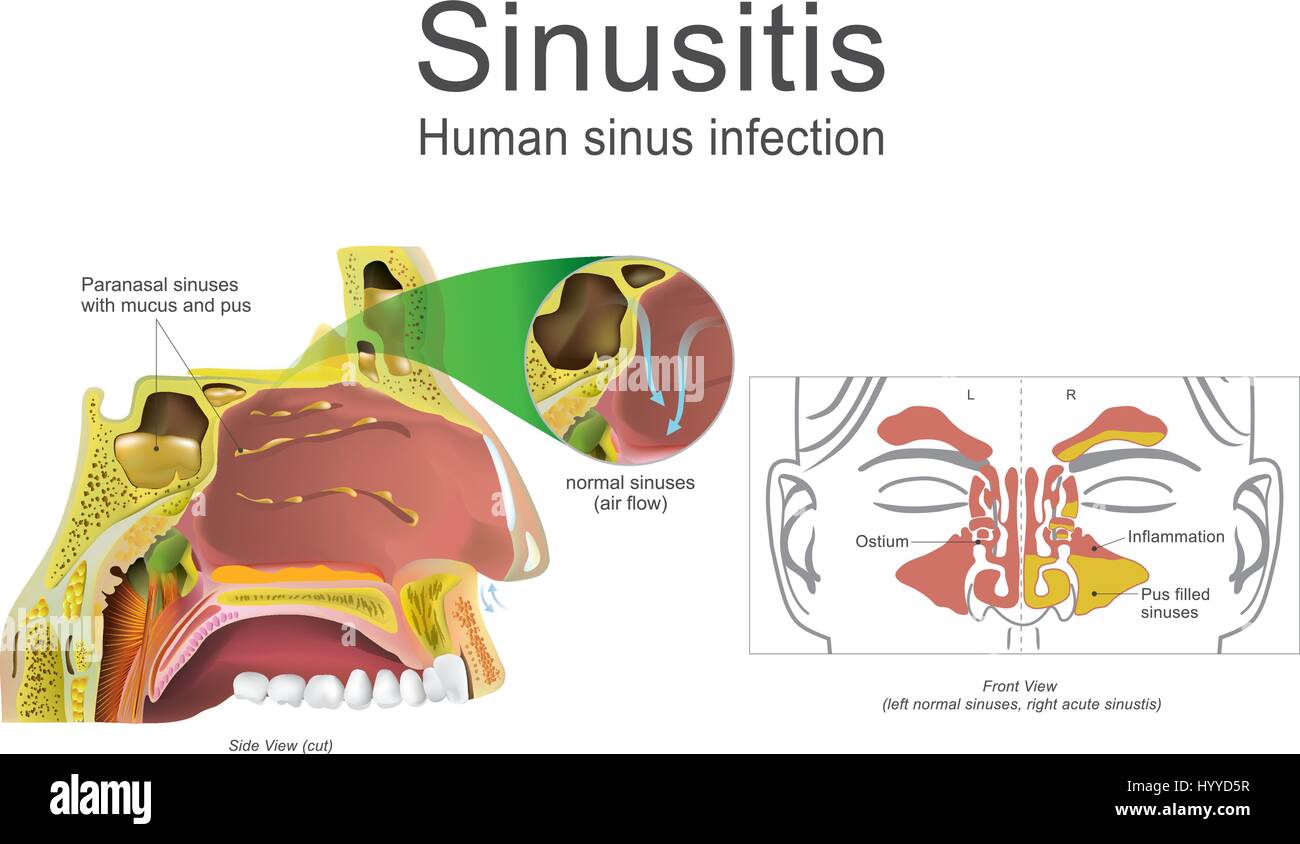

I sintomi comuni includono spesso il muco nasale, un naso ostruito, e dolore in faccia.illustrazione, arte vettoriale. Illustrazione Vettorialehttps://www.alamy.it/image-license-details/?v=1https://www.alamy.it/foto-immagine-i-sintomi-comuni-includono-spesso-il-muco-nasale-un-naso-ostruito-e-dolore-in-faccia-illustrazione-arte-vettoriale-137671347.html

I sintomi comuni includono spesso il muco nasale, un naso ostruito, e dolore in faccia.illustrazione, arte vettoriale. Illustrazione Vettorialehttps://www.alamy.it/image-license-details/?v=1https://www.alamy.it/foto-immagine-i-sintomi-comuni-includono-spesso-il-muco-nasale-un-naso-ostruito-e-dolore-in-faccia-illustrazione-arte-vettoriale-137671347.htmlRFHYYD5R–I sintomi comuni includono spesso il muco nasale, un naso ostruito, e dolore in faccia.illustrazione, arte vettoriale.